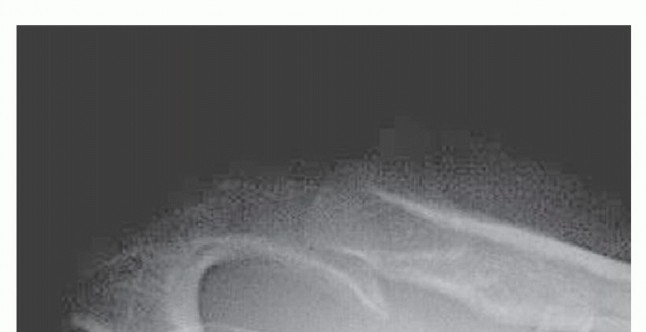

Repair and Reconstruction of Acromioclavicular Injuries DEFINITION About 9% of shoulder girdle injuries invol…